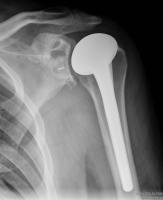

Anatomical Total Shoulder Design

Australian Joint Registry 2024

Revision rate

All diagnosis

| 5 year | 10 year | 14 year | |

|---|---|---|---|

| anatomic TSA stemmed n=7,800 | 8% | 13% | 17% |

| anatomic TSA stemless n= 4,600 | 4% | 5% | - |

| Reverse stemmed n=55,000 | 4% | 5% | - |

For diagnosis OA

| 5 year | 10 years | 14 years | |

| anatomic TSA stemmed n=7,400 | 8% | 13% | 18% |

| anatomic TSA stemless n=4,415 | 4% | 4% | |

| Reverse stemmed n=24,000 | 4% | 5% | 7% |

Reasons for revision anatomic TSA

Instability / dislocation 35%

Rotator cuff insufficiency 28%

Infection 15%

Loosening 12%

Pain 4%

Malposition 1%

Fracture 1%